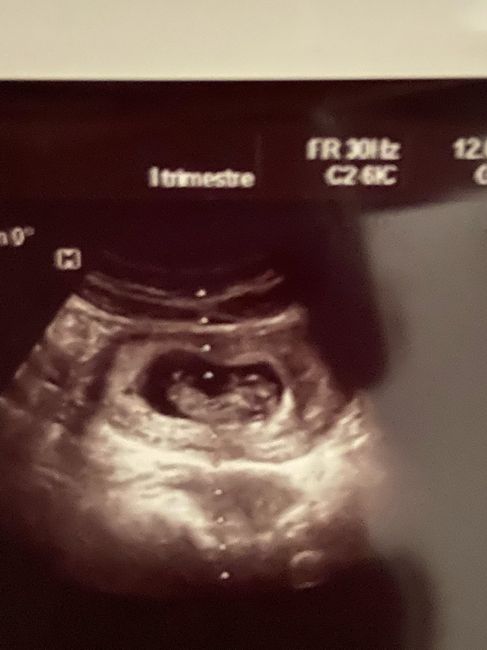

Ciao mamme vi sto mandando la foto dell' ecografia qualcuno mi potrebbe aiutare a vedere se secondo la teoria nub sembra una femmina o un maschio